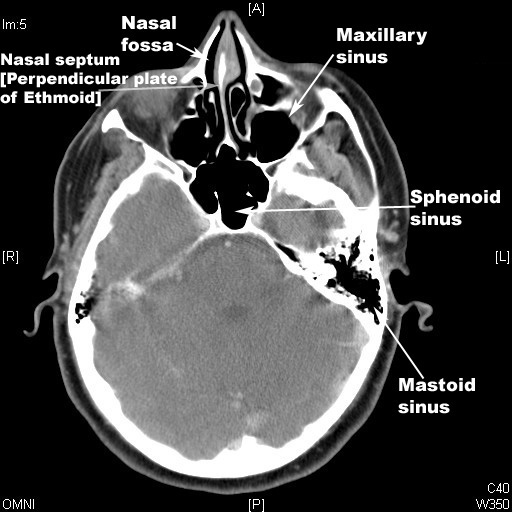

Identify Maxuillary, Mastoid,Sinuses  sphenoid sinuses and Nasal fossa